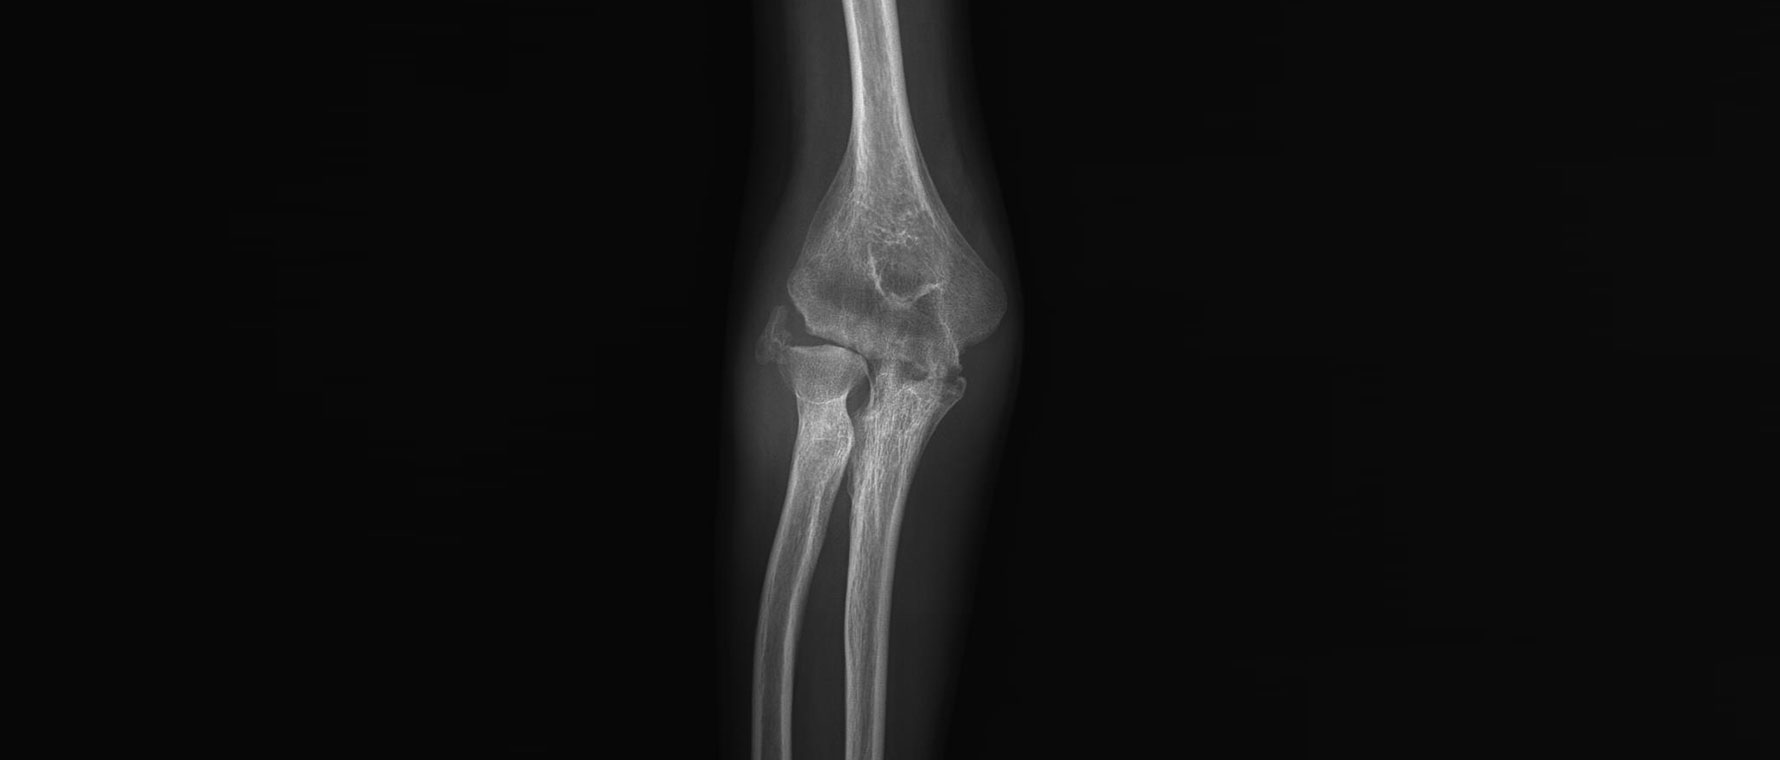

Dirsek Kireçlenmesi

Dirsek kireçlenmesi, eklem yüzeylerinin aşınması sonucu gelişir ve çoğu zaman eski travmalar veya yoğun kullanım sonrası görülür. Hastalarda ağrı, sertlik ve dirseği tam açıp kapatamama şikâyeti olur. Günlük aktiviteler ve iş hayatı etkilenebilir. Tanı muayene ve röntgen ile konur. Tedavide ilaçlar, egzersizler ve enjeksiyonlar uygulanabilir. Dirsek hareketleri 30 dereceden fazla açmada kısıtlılık ve 130 dereceden fazla kapatmada kısıtlılık varsa ameliyat önerilir. Artroskopik ya da açık ameliyatlarla kireçlenmeler temizlenir. Çok kısıtlı hastalarda dirsek protezi ameliyatı uygulanabilir ya da vücuttan alınan doku parçaları ile eklem yüzleri yenilenebilir. İleri ve ağrılı vakalarda ise tedavi dirsek ekleminin dondurulmasıdır.